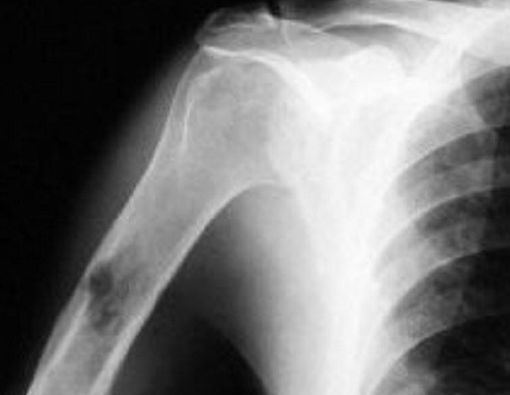

KlikDokter.com - Kanker tulang dapat menyerang tulang manapun di dalam tubuh, namun pada umumnya menyerang tulang panjang pada lengan dan tungkai.

Osteosarkoma. Berasal dari sel-sel tulang dan umumnya menyerang anak-anak dan remaja.

Tulang patah